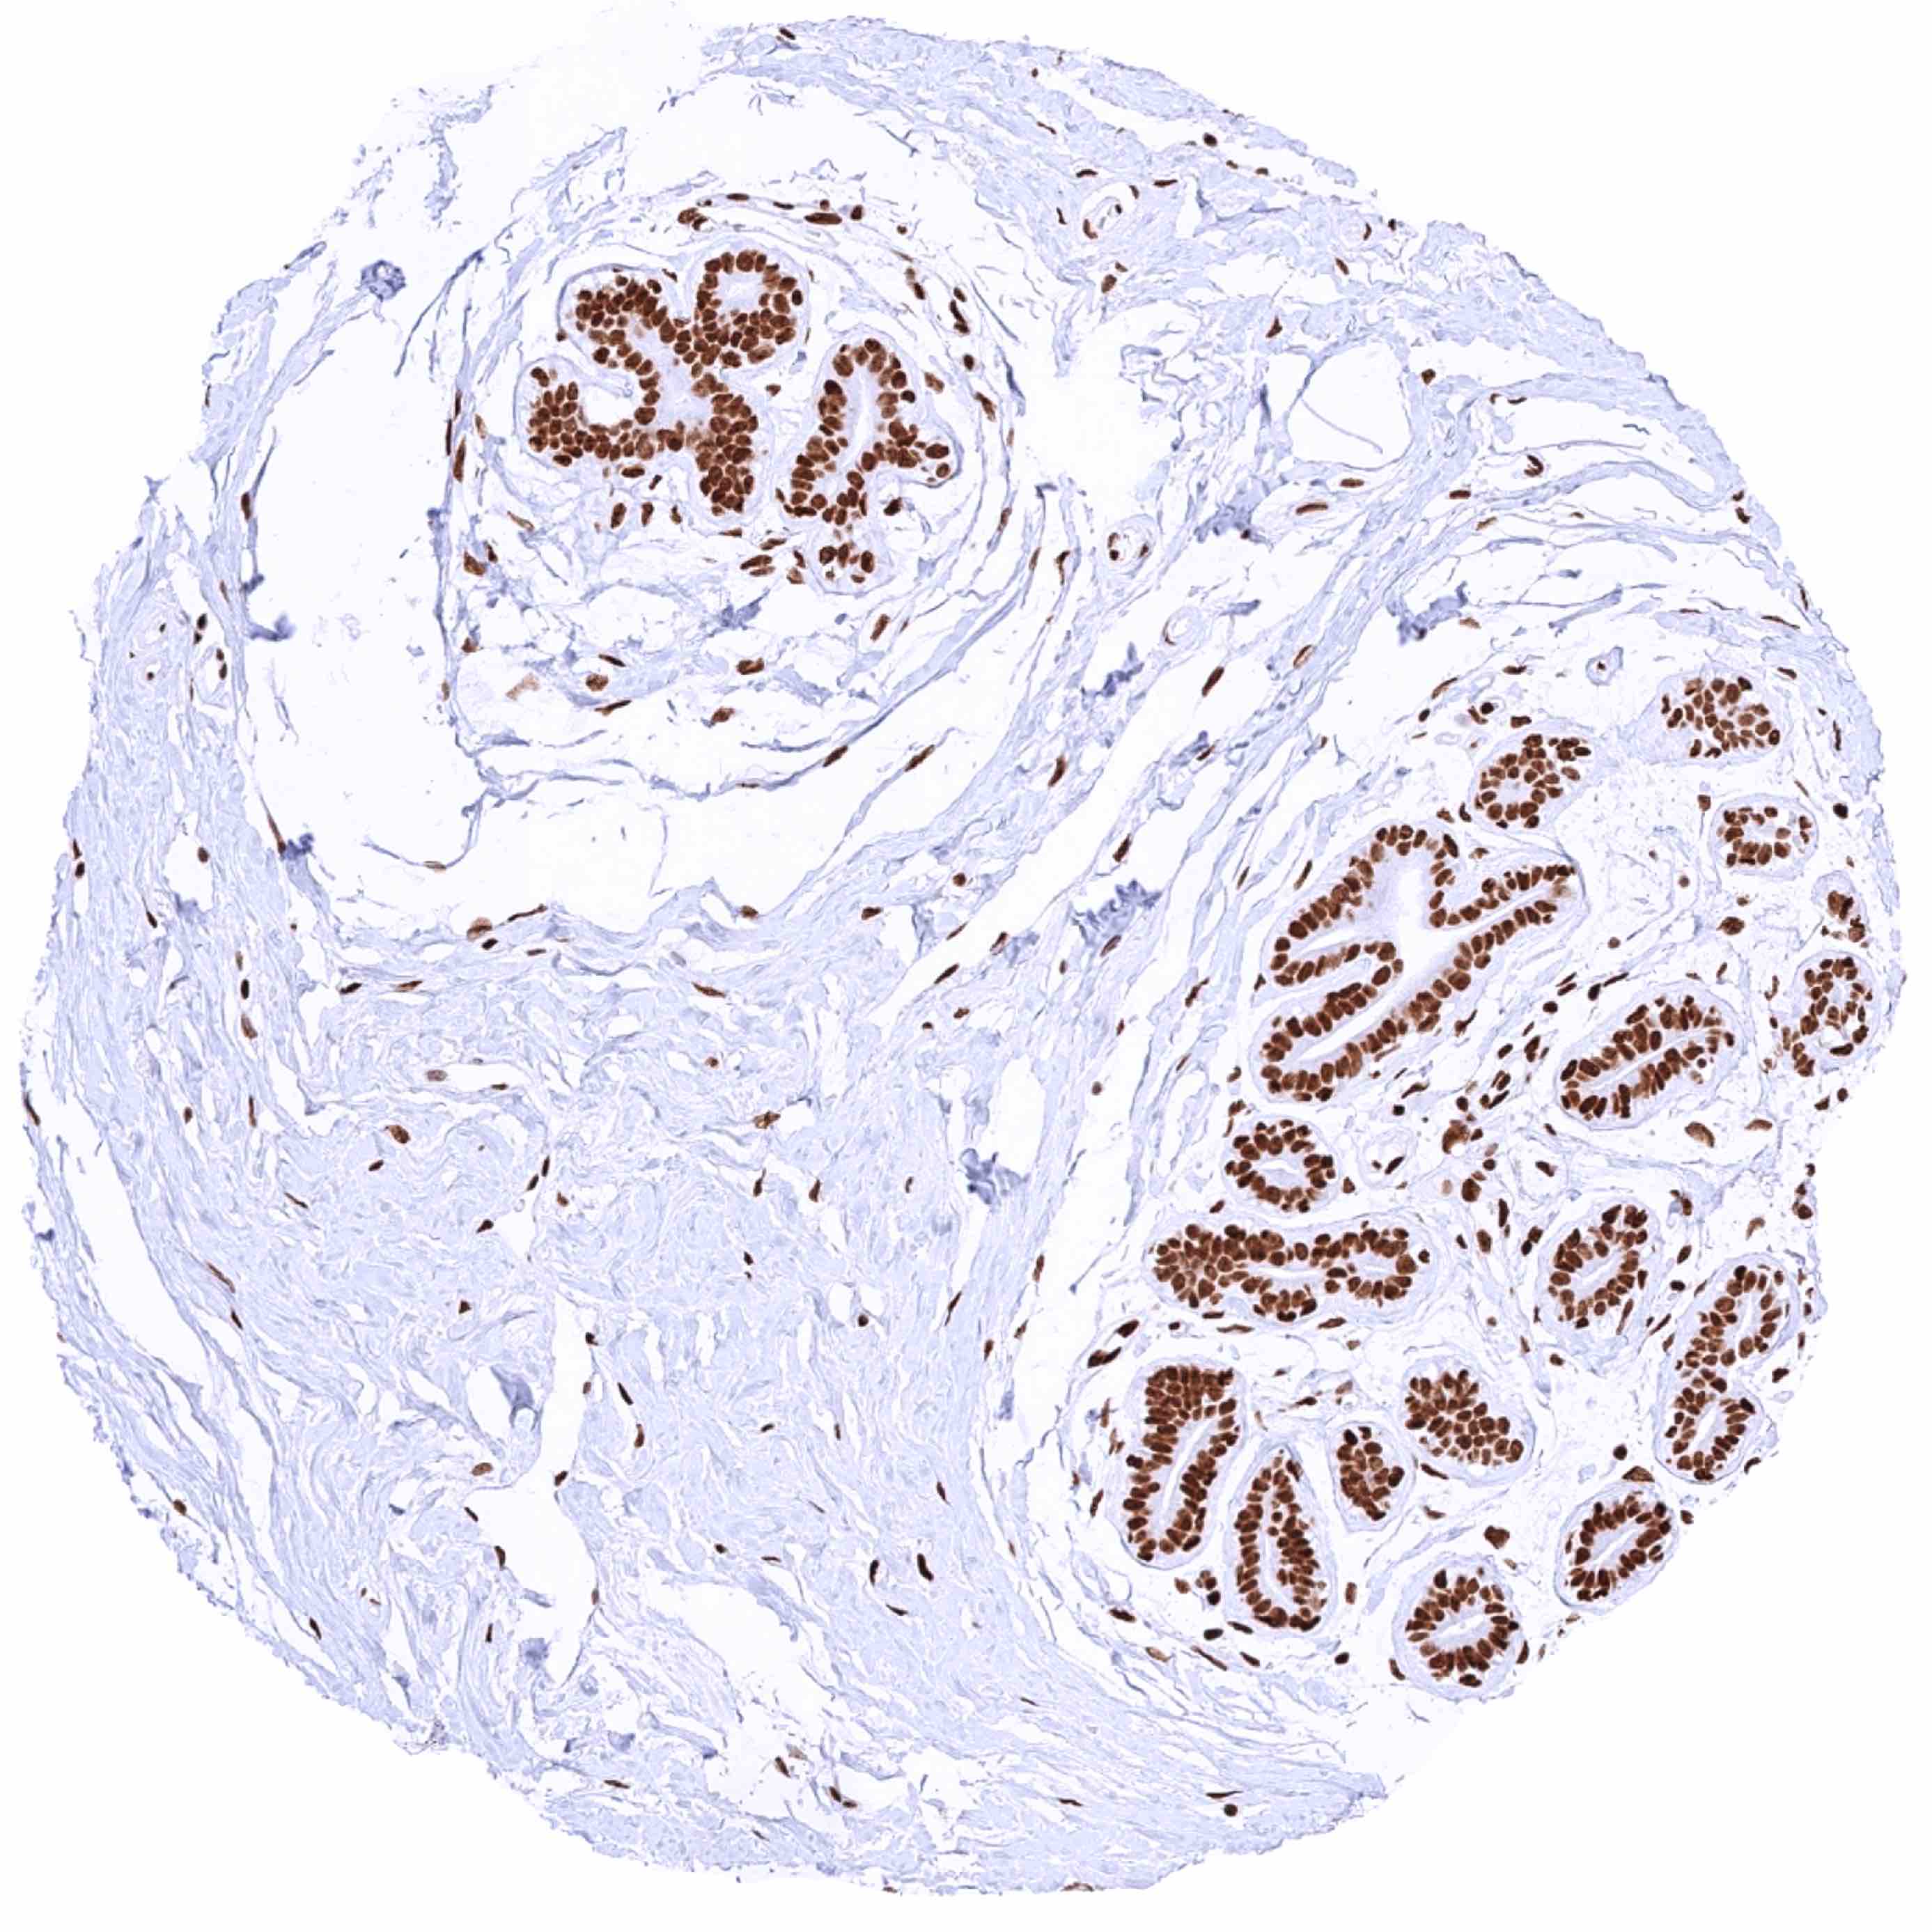

Prostate – Significant nuclear HMGB1 staining of all cells. Staining is particularly low in acinar cells and highest in basal cells